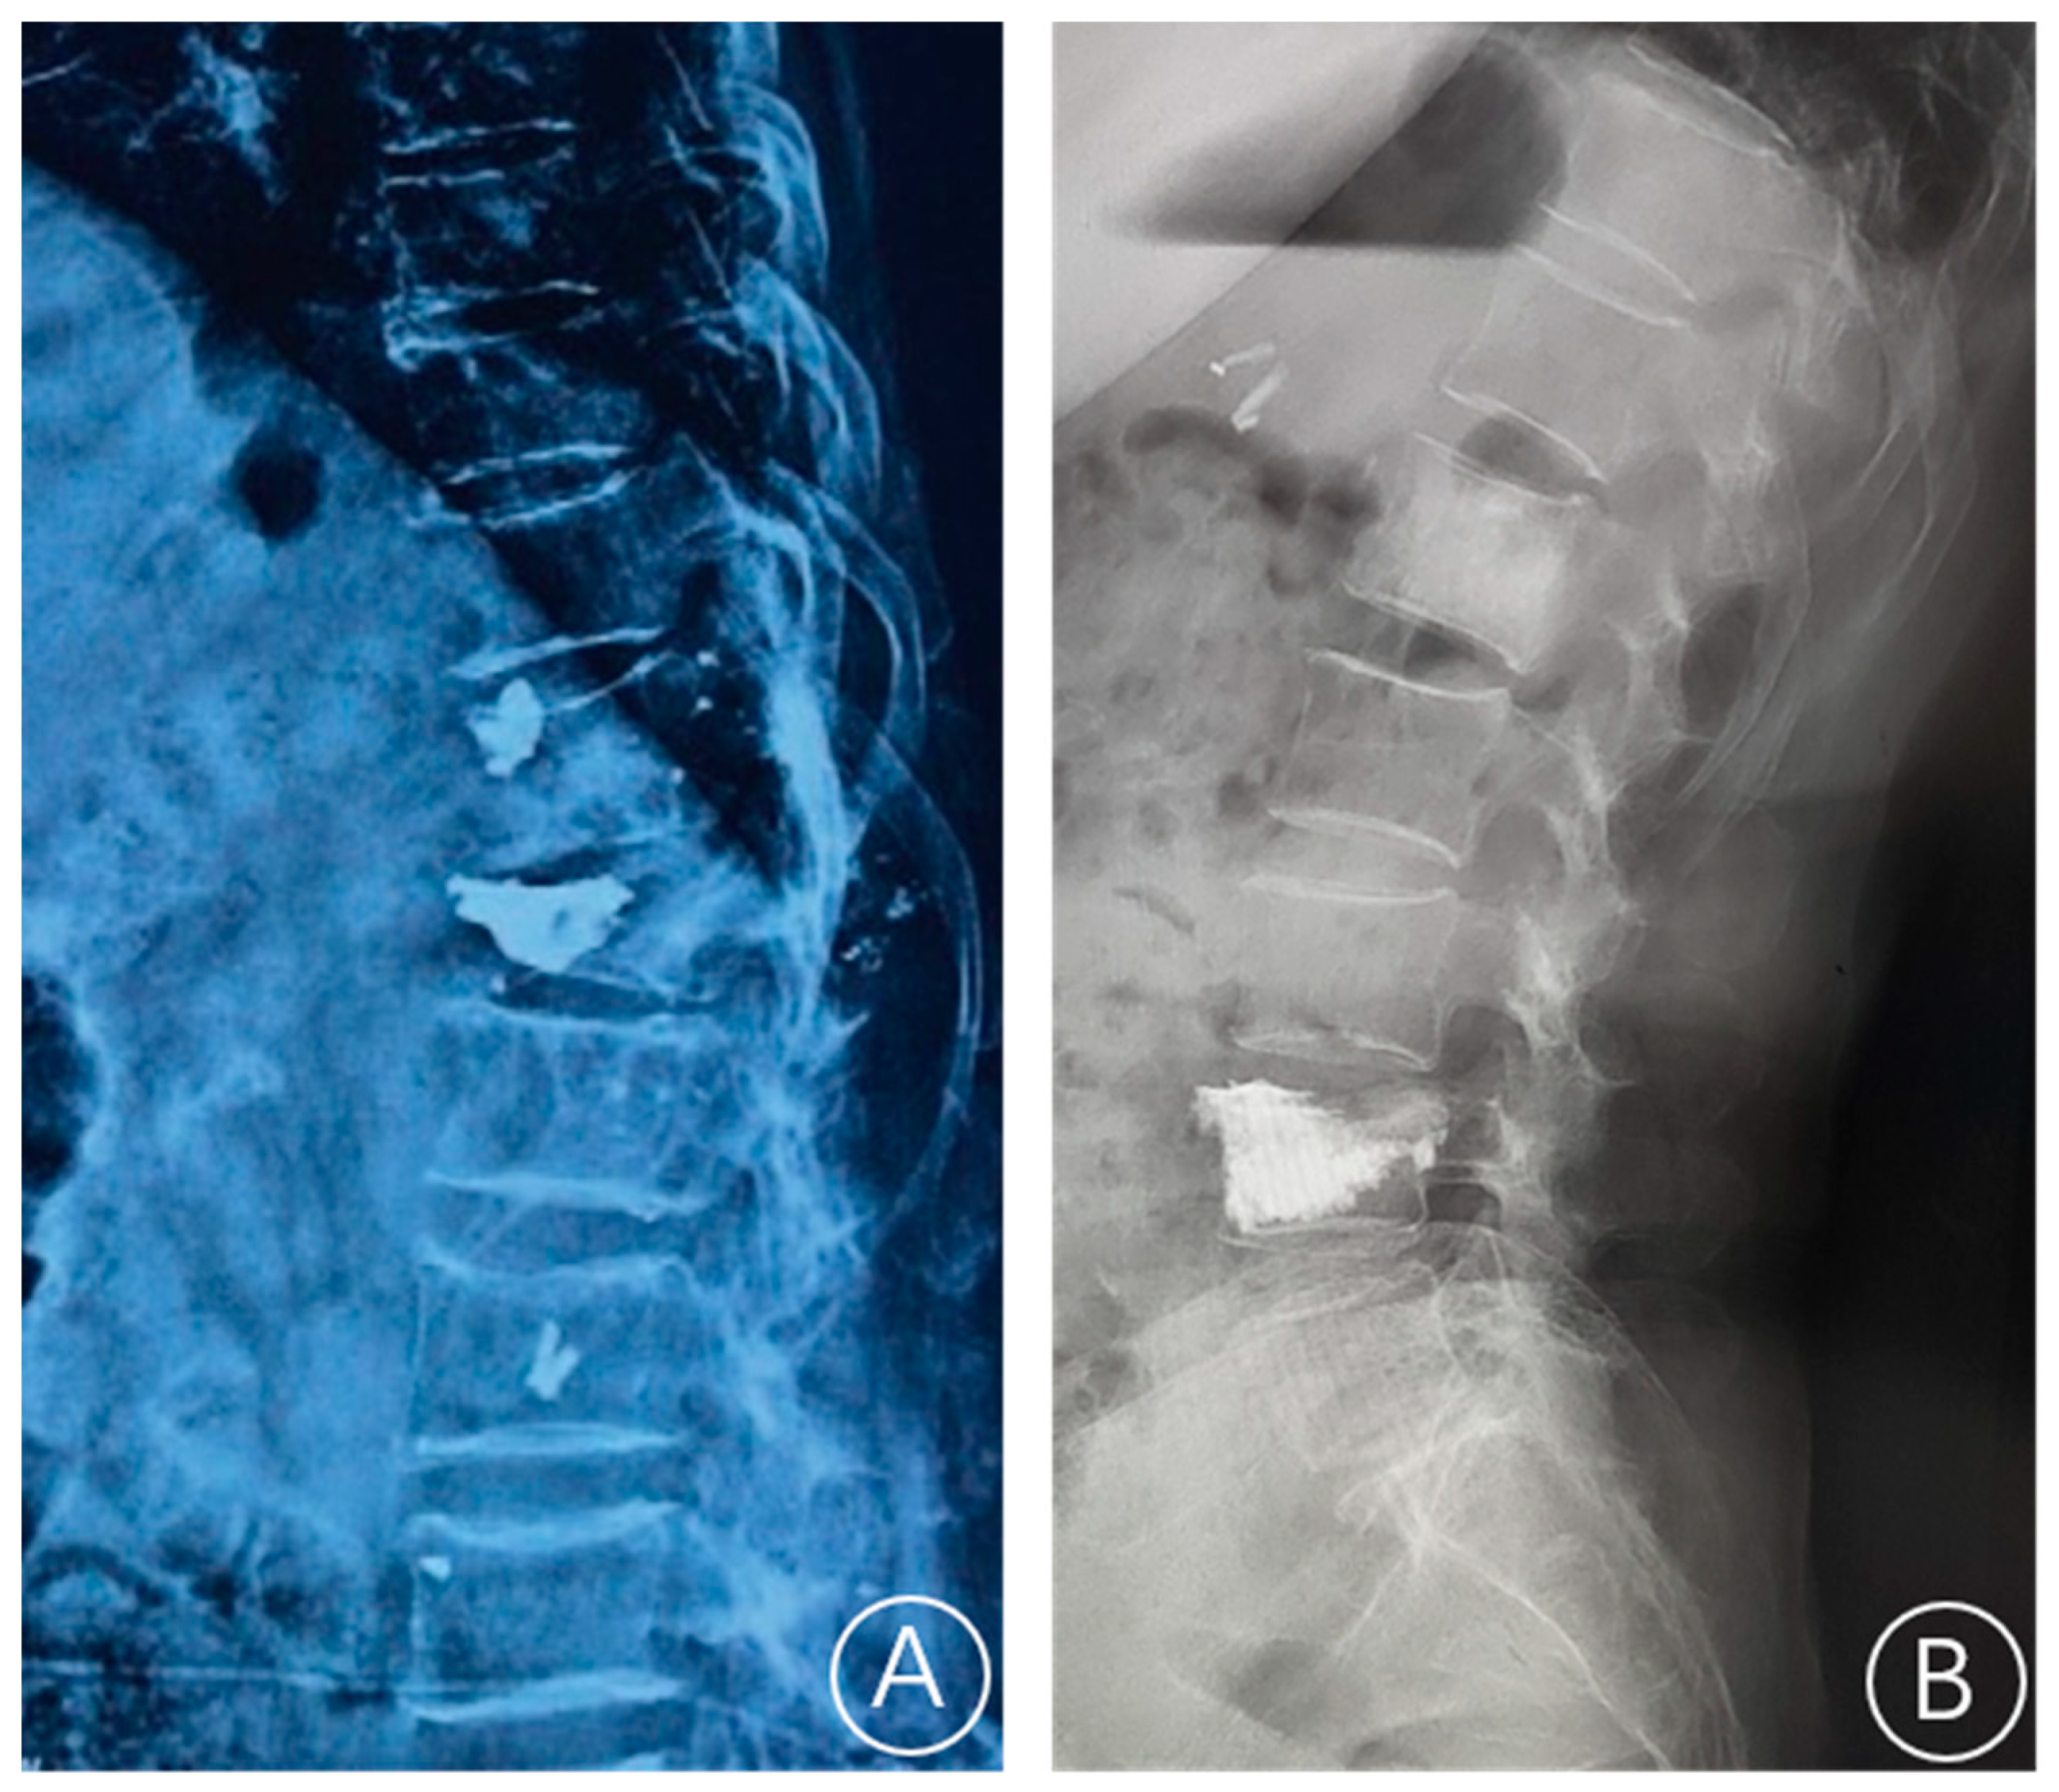

2.2. Bone Cement Displacement Diagnostic Criteria

2.3. Treatment Method